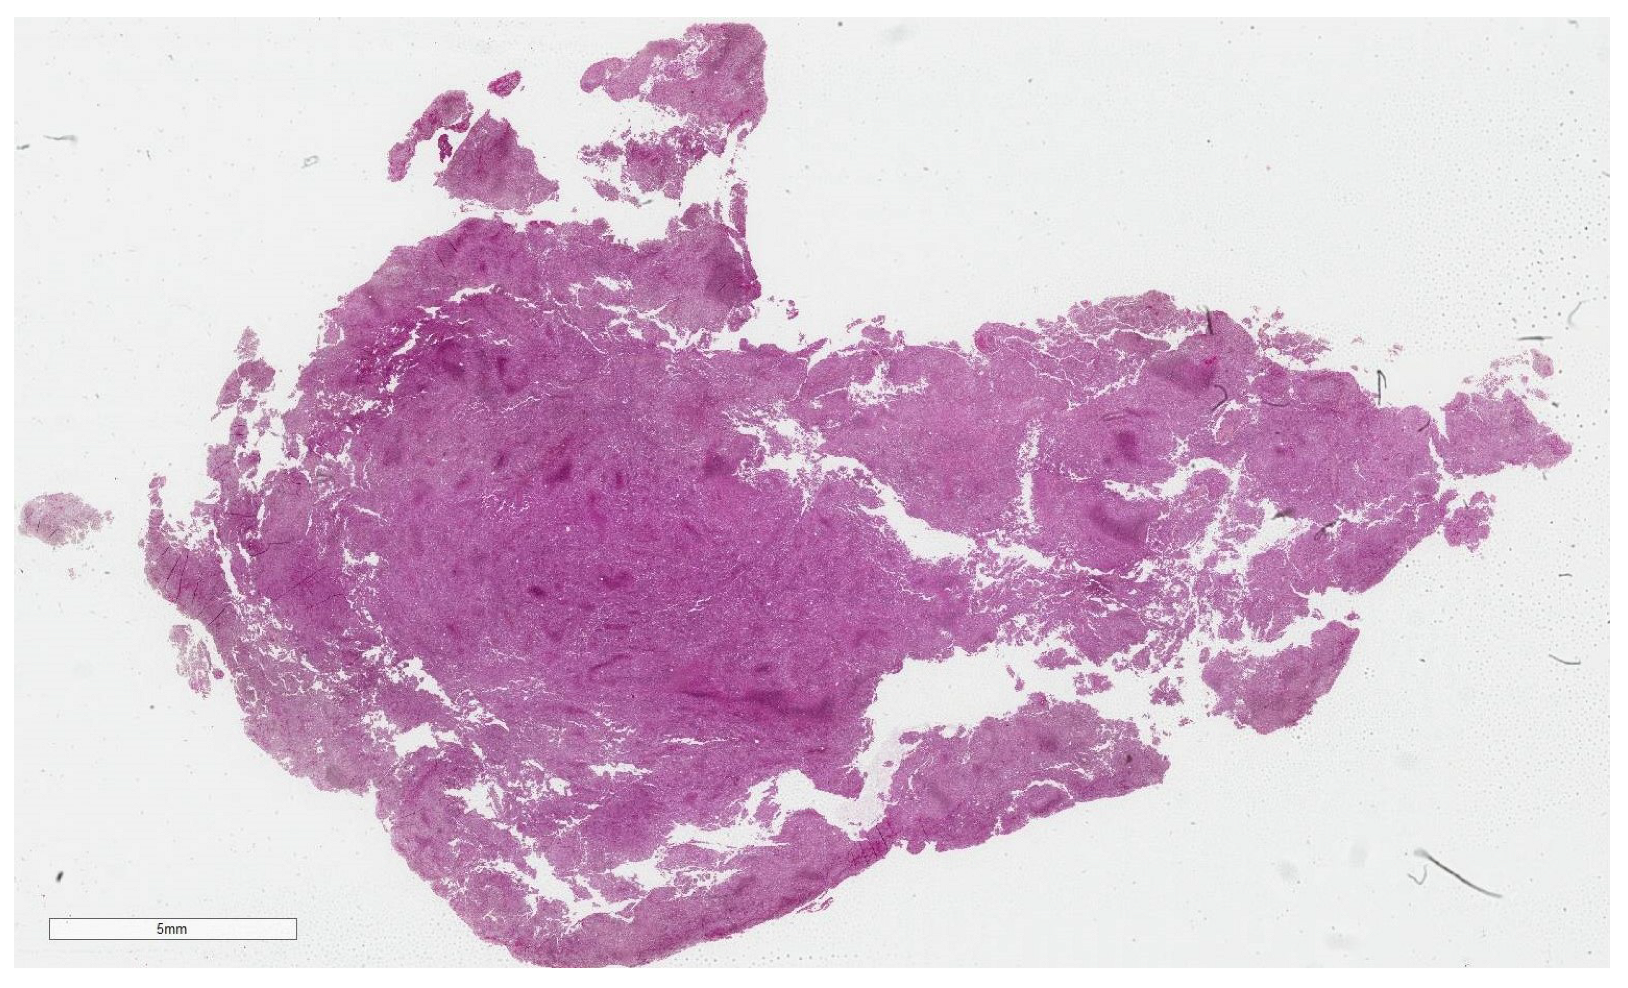

2.3. Dataset